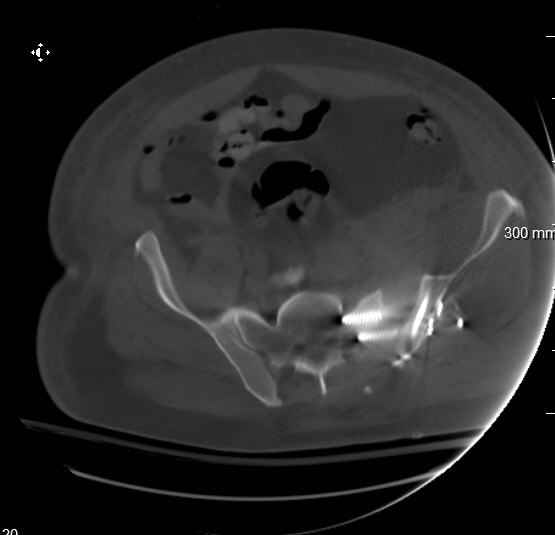

Request for more images.. Axial and coronal recon (pt in binder.)

Hello gentlemen- Case is 52 YO male, fell out of treestand while deerhunting. He is 6 ft, approx. 260-275 lbs. Was hemodynamic unstable at local ER, sent to our Trauma center where circumferential pelvic binder placed and pt. stabilized with fluid, blood, and rewarming. Angiography not performed. An extraperitoneal bladder disruption was found, uro elected to treat non-operatively. Initial xray (not shown) demonstrated 5-7 cm wide at symphysis and SI joint. The first image attached is of CT once binder is in place. On post trauma day 5 the pt was taken to OR for ORIF of his iliac wing fracture and SI dislocation. The swelling/3rd spacing of fluid in the area of symphysis was profound, but quite acceptable posteriorly. Patient was prone for procedure, as I thought too difficult to fix the wing in lateral position. Of course the repair of wing was easy, but reduction of SI very demanding. The Floro images document the residual lack of reduction. That was the closest I could get it using 6mm joystick in wing, and clamp on sacrum and clamp through notch. The fixation was (initially) rigid. Anterior ex fix with supra-acetabular pins was placed due to condition of soft tissues, massive "beer-belly" overhanging the crest. Post trauma day ten patient's xray shows failure of posterior construct. Plan was to perform revision orif once soft tissues resolve considerably for full anrterior fixation and posterior fixation. However, while Im away for holiday (on Post trauma day 15), pt is developing septic clinical appearance, and trauma suspects pelvic abcess near symphysis and performs I and D - finds nothing but no primary closure performed. Posterior tissues/incision continue to look healthy. Now is post trauma day 17, pt is still tubed/on dopamine/and wbc still elevated, anterior incision still packed open. Clearly must get to bottom of possible sepsis, but then what? Thanks for you time - sorry for such lengthy clinical description. Thomas Schaller Kalamazoo, Michigan

5. Your caudal iliosacral screw is/was in his spinal canal... it's low and posterior and the lateral fluoro image confirms this... a postop CT will show it (or it's trail at this point)... canal screws do not hold.